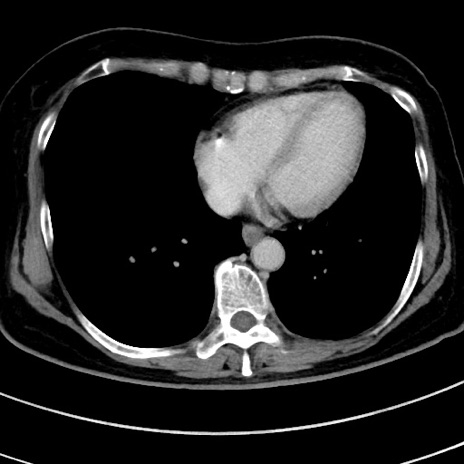

冠状断像

【症例】 60歳代女性

【主訴】むかつき、みぞおちの痛み

【現病歴】3日前よりむかつきがあり、食事がとれない。

【既往歴】糖尿病

【身体所見】発熱なし、心窩部圧痛軽度あるも、腹膜刺激症状なし。

【データ】WBC 7400、CRP 1.92